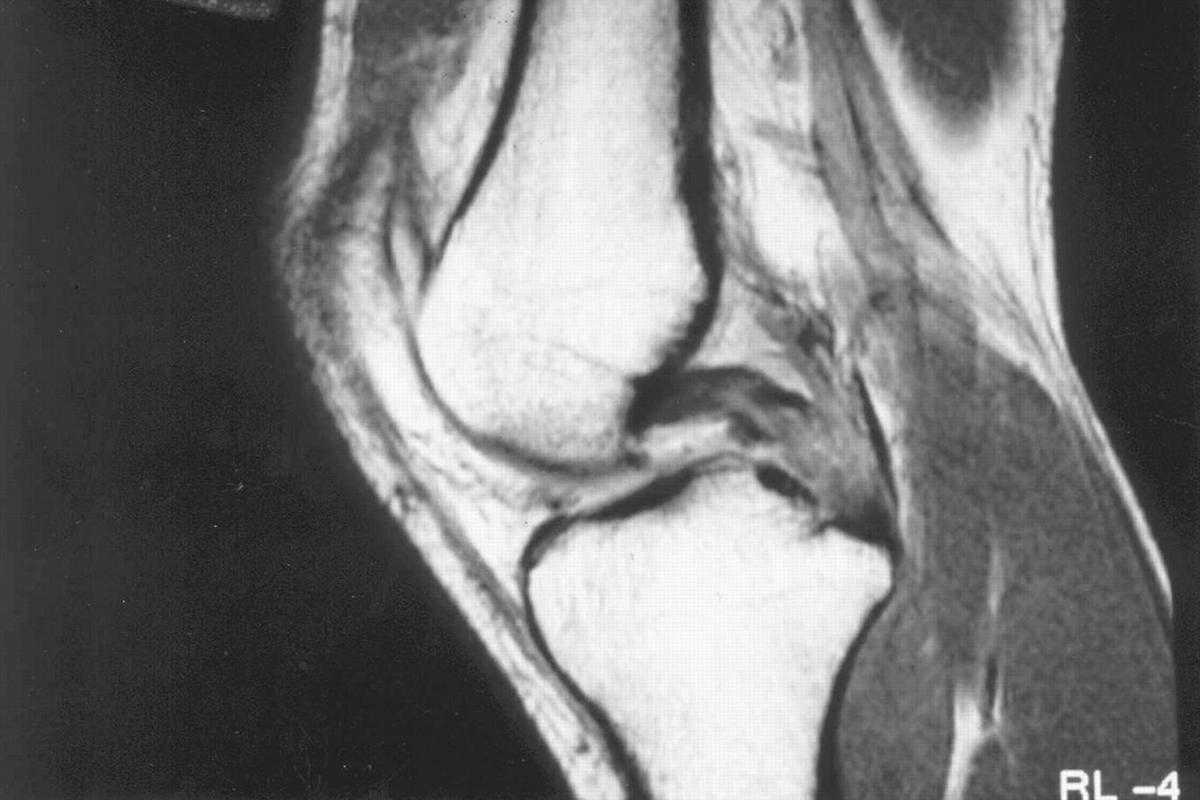

Απεικονιστικά, οι ακτινογραφίες είναι χρήσιμες για αποκλεισμό καταγμάτων. Η μαγνητική τομογραφία (MRI) αποτελεί τη μέθοδο εκλογής, καθώς επιβεβαιώνει τη ρήξη, εκτιμά τη βαρύτητα και ελέγχει για συνοδές κακώσεις. Σε χρόνιες ή σύνθετες περιπτώσεις, η αξονική μπορεί να βοηθήσει σε ειδικές οστικές εκτιμήσεις και σχεδιασμό.